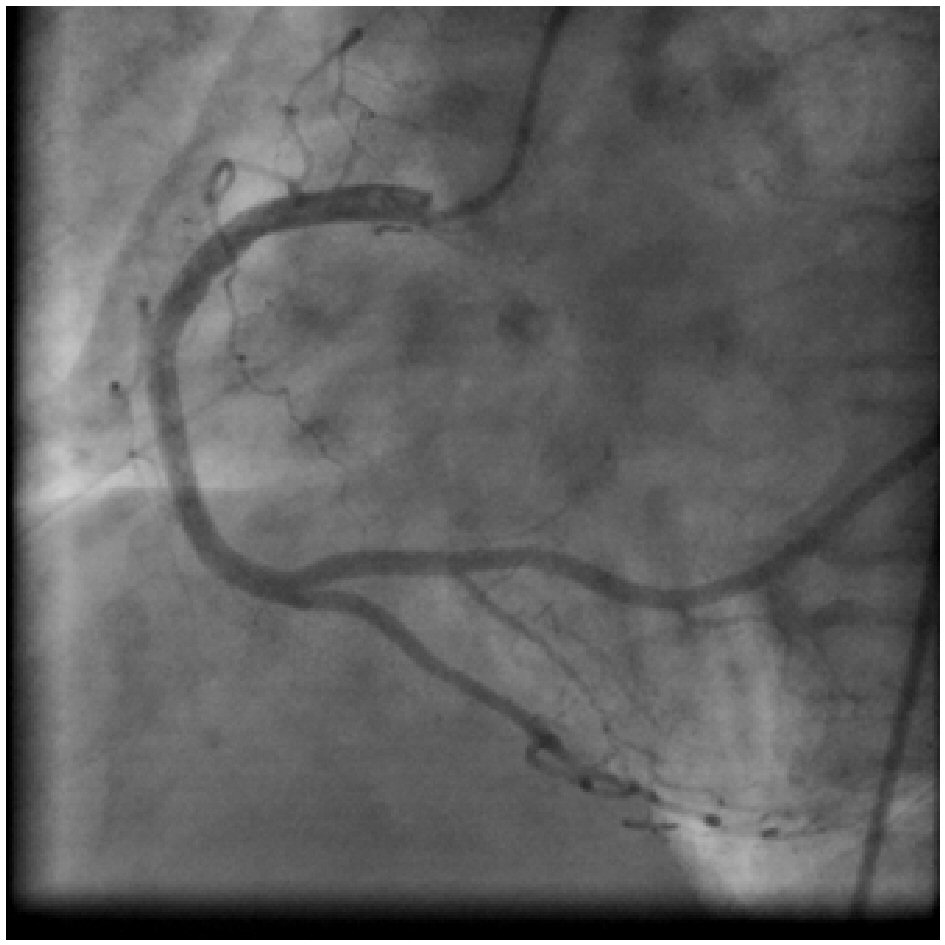

A 48-year-old lady, non-hypertensive and non-diabetic, presented with chest pain on exertion since 4 months. Physical examination did not reveal any abnormal findings. Cardiovascular examination was normal. Laboratory parameters for lipid and renal function were normal. Her electrocardiogram showed a sinus rhythm with no significant ST-T changes. Echocardiography revealed no regional wall motion abnormalities with left ventricular ejection fraction of 60%. Stress (treadmill) test showed positive result for inducible ischemia by Bruce protocol at 9 METS. So she was further investigated for coronary artery disease. Coronary angiography revealed that the left main and left anterior descending (LAD) coronary arteries appeared normal (Fig. 1, 2). The RCA was a large super-dominant vessel which crossed the left atrioventricular groove and supplied the inferior and posterolateral walls of the left ventricle (Fig. 3, 4). The LCX was not visualised (Fig.1, 2). Aortic root angiography did not reveal any anomalous LCX (Fig. 5). However, angiography using a 64-slice multi-detector computed tomography (MDCT) performed on the following day confirmed absence of the LCX. The posterior descending artery (PDA) and posterior left ventricle (PLV) branches were prominent. The PLV supplied the posterolateral wall of the left ventricle (Fig. 6). Hence patient was diagnosed a case of congenital absence of the LCX with super-dominant RCA without evidence of atherosclerotic coronary artery disease. The patient was advised medical management and regular follow-up.

![]() Click for large image | Figure 4. Right coronary angiogram in RAO cranial view: showing a super-dominant RCA with large posterolateral branches perfusing the posterolateral and lateral walls of the heart (usually supplied by the left circumflex artery). |